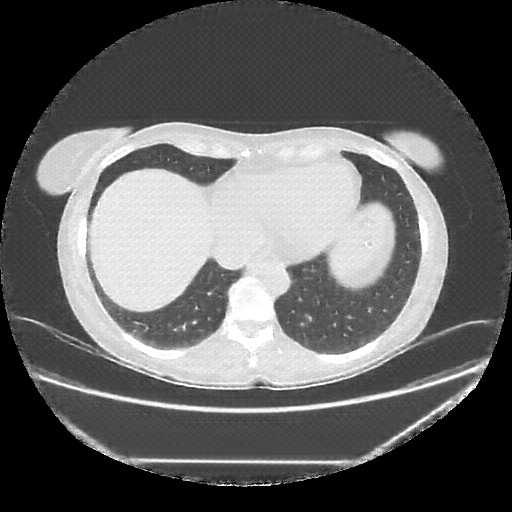

Reconstructed NATIVE CT scan (cycle consistency)

No window - Raw intensity values

Lung window (WL -600, WW 1500 β†’ Low βˆ’1350, High +150)

Mediastinum window (WL 40, WW 400 β†’ Low βˆ’160, High +240)